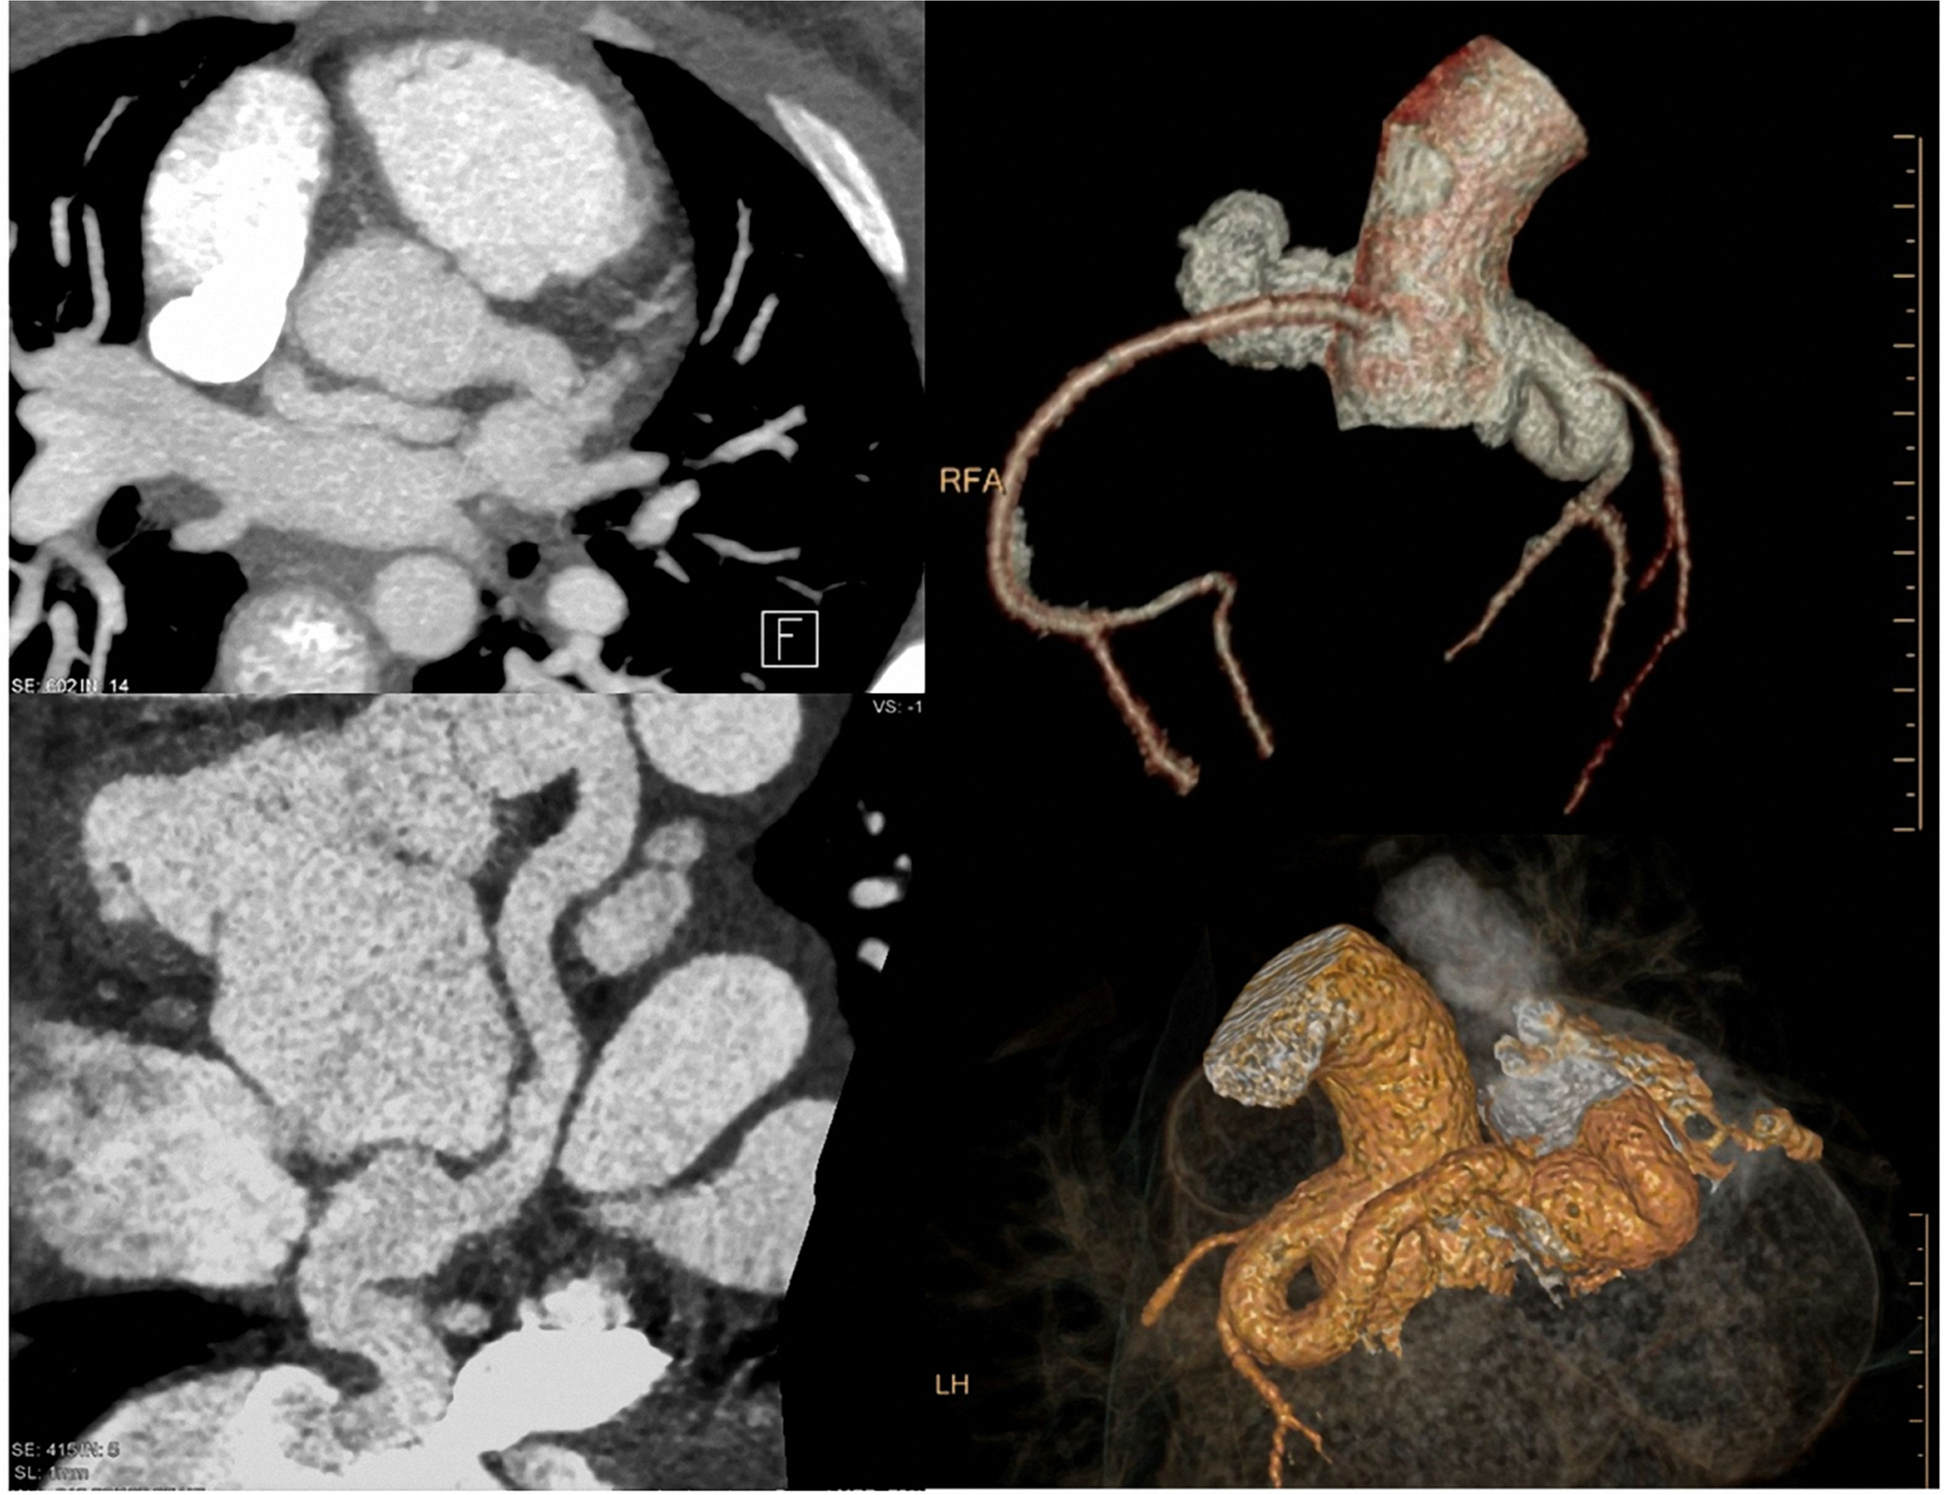

Morphologic alterations beyond CHD—coronary fistulas

Coronaries and their assessment are still an unmet need by cardiac MRI. Here, cardiac CT is also in pediatric populations the method of choice for non-invasive assessment. A typical example is an 11-year-old girl (Fig. 13), who was referred to our department due to reduction of cardiac function and palpitations. Non-invasive echocardiography showed an unclear coronary situation with a high suspicion of coronary shunting. In an interdisciplinary discussion, the decision to apply cardiac CT (and not cardiac MRI) was made for this situation. The 3D reconstruction demonstrates a coronary fistula with an enlarged sinus artery and a left–right shunting. The origin was the left main branch with a mouth into the right atrium just lateral the cavo-atrial connection. The radiation dose was below 1 mSv due to the application of dose reduction software (iterative reconstruction) during data acquisition. Minimal-invasive therapy was planned.

Fig. 13

(Planning, dose monitoring (left upper and lower row), axial and paracoronar 2D MIP reconstructions (middle), and 3D VRT reconstructions (right)): 11-year-old girl. Previous surgical repair of a VSD. Now suspected (echocardiography—not shown) coronary fistula. CTCA with dose reduction software, resulting in a low radiation dose (total DLP 63 mGycm ~ 0.8 mSv). CT allows a complete and rapid representation of even highly complex anatomic alterations (in one breathhold)